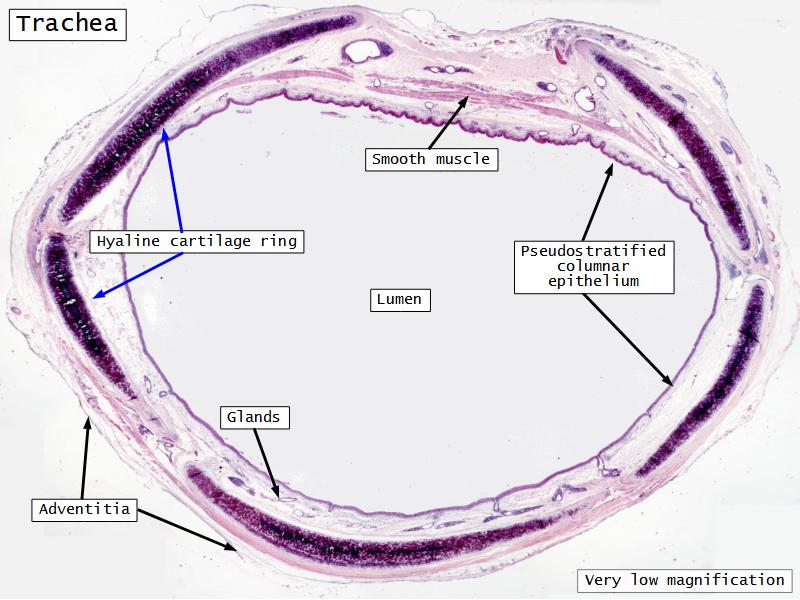

Respiratory epithelium

- Pseudostratified

- Ciliated

- Columnar

- Epithelium with

- 4 Cells

- Ciliated columnar cells

- Non-ciliated columnar cells

- Goblet cells

- Basal cells

Trachea

Bronchi - Transitions

- Intrapulmonary bronchi

- Irregular cartilage

- Respiratory epithelium

- Glands